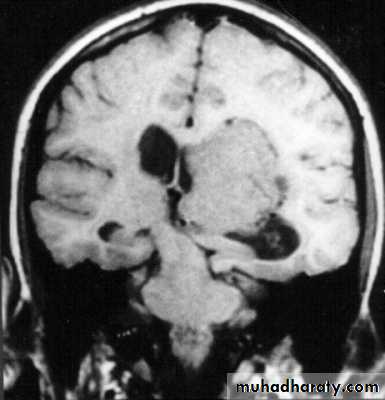

1. Brain Oedema (Cerebral Swelling)

Can be local (around a haematoma) or diffuse.

It is due to intracellular or extracellular accumulation of fluid.

It leads to raised intracranial pressure, which itself causes problems.

It is more common and more dangerous in children.